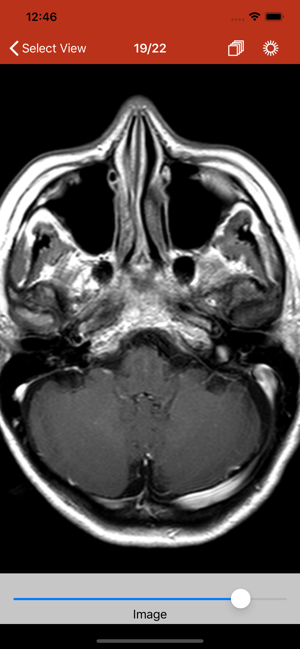

This app lets you import and show DICOM images from cat scans or magnetic resonance imaging. The imp

The app shows the images and the information stored in DICOM files which are used for Magnetic reson